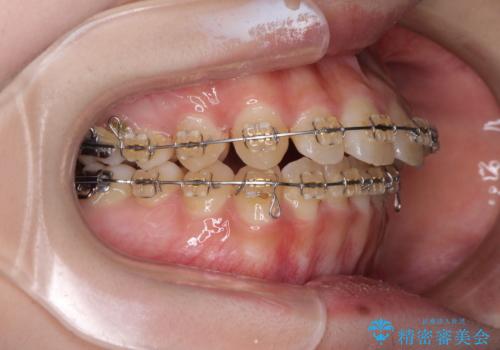

- 矯正装置

- 審美装置

- 2年6ヶ月

- 大学病院にて装置を装着したものの、治療が十分に受けることができないとのことで転院をされた患者様です。

上顎歯列が前方にあり、口元が閉じにくくなっていたため、既に装着されている装置を使用して上顎歯列全体を後方に移動させていくこととしました。